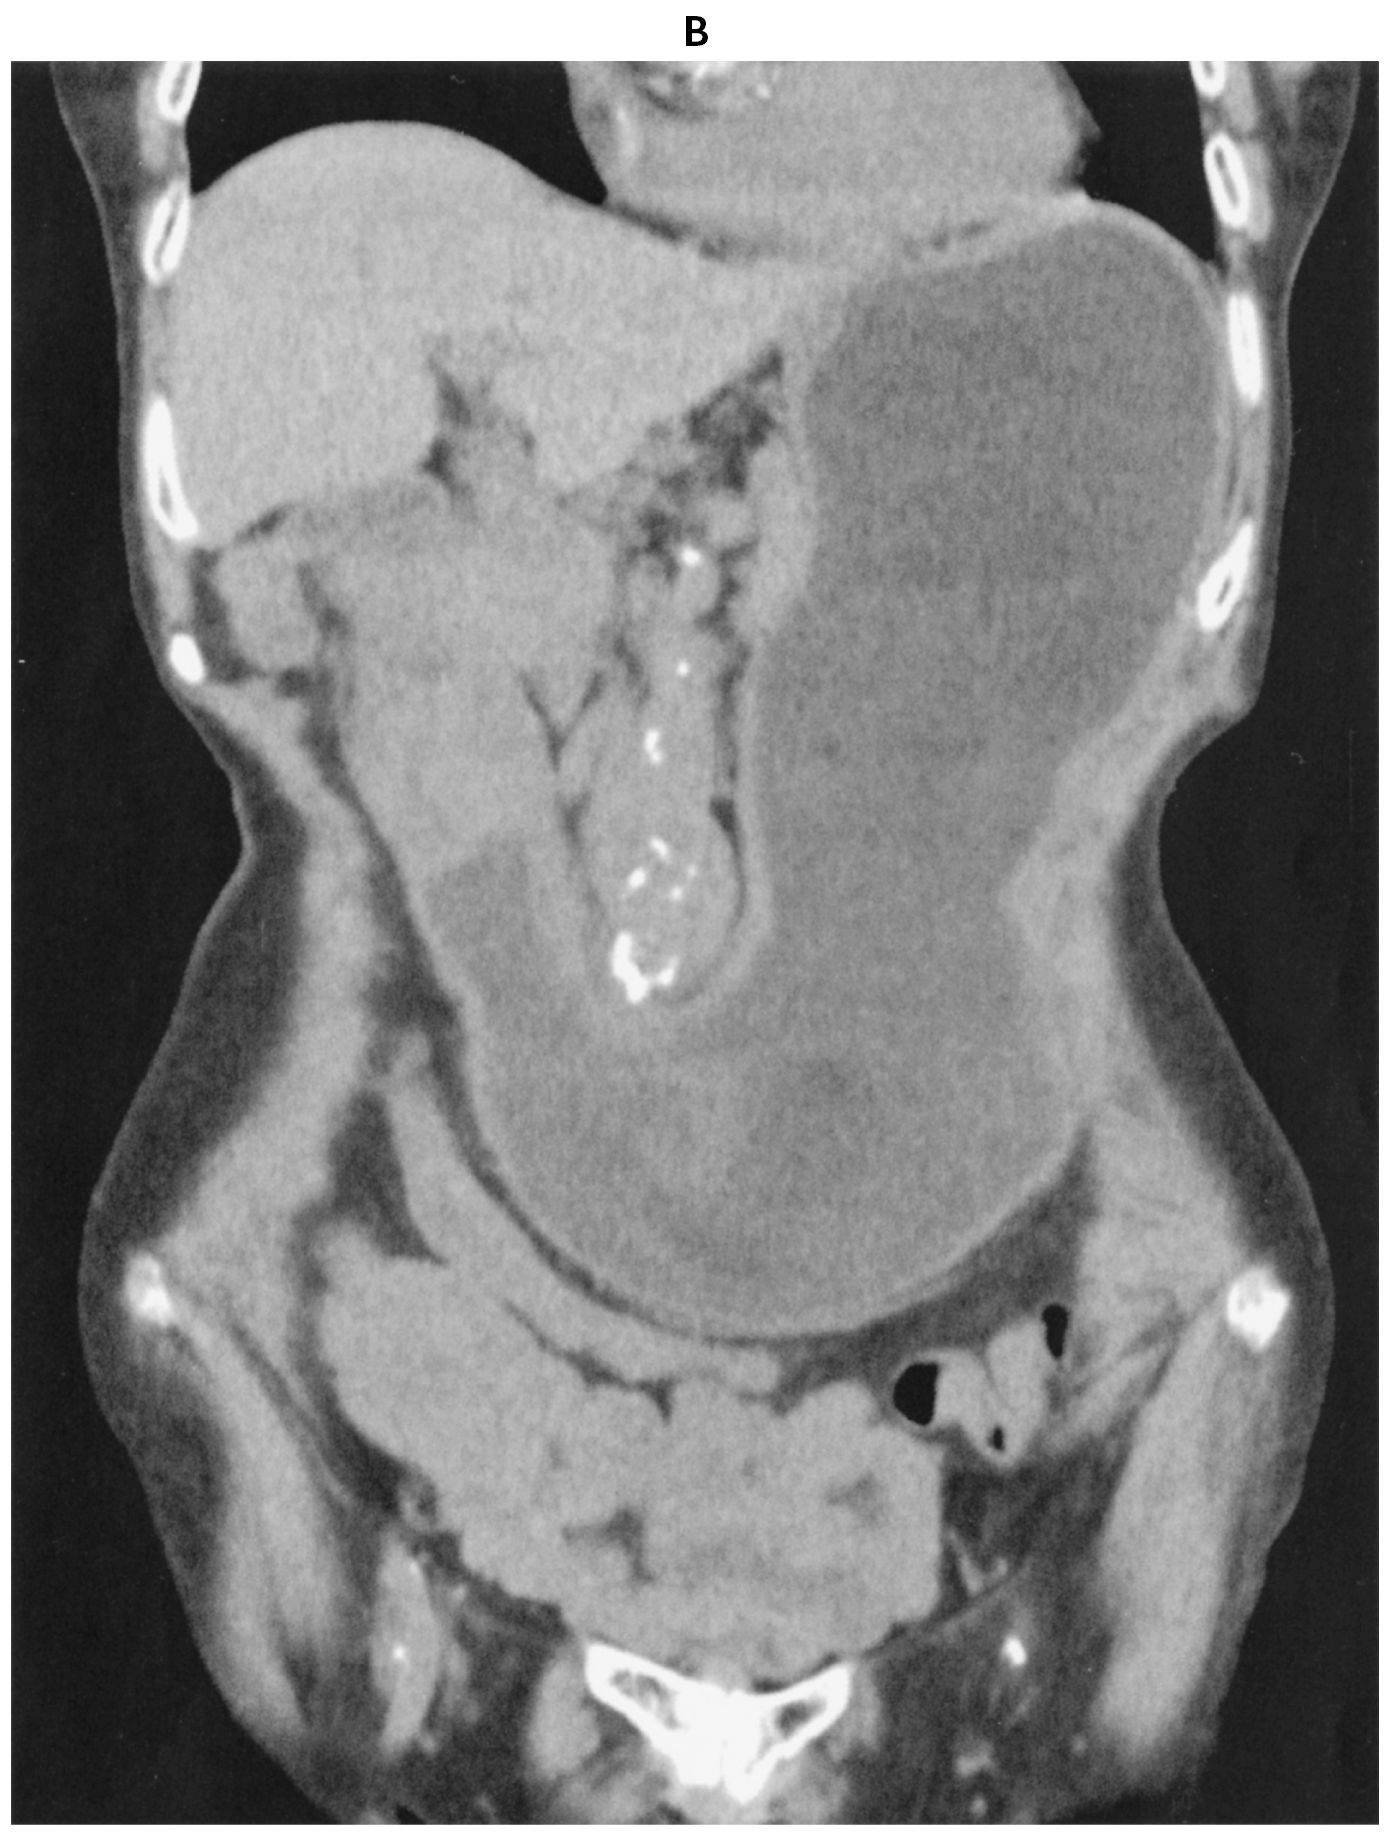

88歳の女性。呼吸困難を主訴に救急車で搬入された。3か月前から心窩部痛があり,2か月前には悪心で食事が摂れなくなり,3週間前から嘔吐を繰り返すようになった。睡眠中に嘔吐し,呼吸困難が出現したため家族が救急車を要請した。喫煙歴と飲酒歴はない。意識は清明。身長148cm,体重36kg。1か月で6kg体重が減少した。体温36.2℃。心拍数108/分,整。血圧98/48mmHg。呼吸数12/分。SpO2 94%(マスク5L/分 酸素投与下)。呼吸音は前胸部右側で減弱し,coarse cracklesを聴取する。腹部は膨隆し,圧痛を認める。尿所見:蛋白(-),糖(-),ケトン体2+,潜血(-)。血液所見:赤血球418万,Hb 11.9 g/dL,Ht 38%,白血球5,500,血小板30万。血液生化学所見:総蛋白6.4g/dL,アルブミン2.8g/dL,総ビリルビン0.5mg/dL,AST 26U/L,ALT 18U/L,LD 202U/L(基準124~222),ALP 110U/L(基準38~113),尿素窒素28mg/dL,クレアチニン1.4mg/dL,血糖88mg/dL,Na 132mEq/L,K 4.6mEq/L,Cl 98mEq/L,Ca 8.8mg/dL,P 2.7mg/dL,CEA 18.6ng/mL(基準5以下),CA19-9 36U/mL(基準37以下)。CRP 3.0mg/dL。腹部単純CT(A)(B)を下に示す。気管内吸引で食物残渣を多量に認め,その後低酸素血症は改善した。2週間後に開腹手術を行うことにした。低栄養に対して,栄養サポートチーム〈NST〉に介入依頼をした。